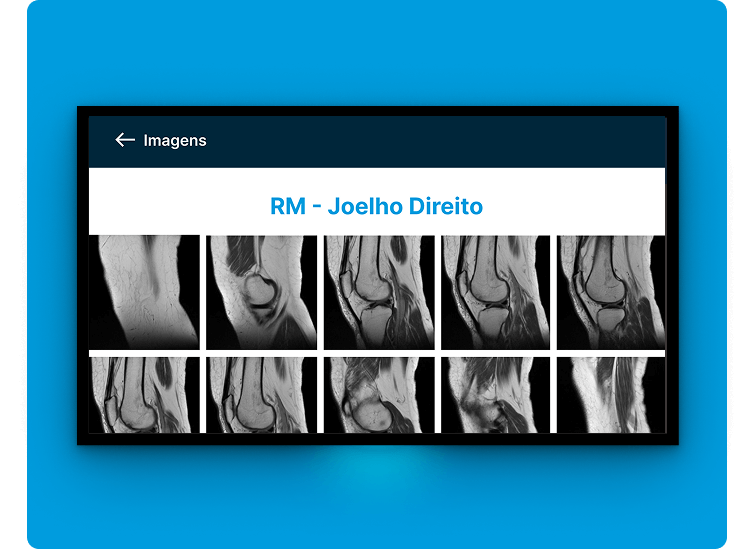

La fusión DICOM PET-CT permite la combinación y sincronización de ambas en una sola imagen o conjunto de datos. Realice análisis más completos superponiendo información metabólica de PET sobre estructuras anatómicas visualizadas por TC para una mejor localización y caracterización de anomalías, como tumores, proporcionando información funcional y estructural en una sola imagen.

Accede a exámenes e informes desde donde estés, de forma cómoda y sin burocracia.

Accede a los exámenes desde tu computadora de escritorio o usando tu computadora portátil dondequiera que estés. Acceda a informes, archivos adjuntos e imágenes en calidad original, además de todas las herramientas que necesita, dondequiera que vaya.

Calidad diagnóstica en cualquier lugar, en cualquier momento y en el menor tiempo posible.

Calidad diagnóstica en cualquier lugar, en cualquier momento y en el menor tiempo posible.